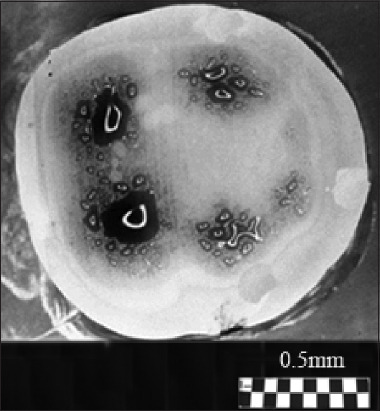

Results: The dentinal tubules were shown to originate from the center of the cusps in both molar and premolar teeth, forming S-shaped fiber bundles with axial-radial symmetry. These bundles were arranged along axes, extending from the pulp toward the centers of the cusps of the tooth crown. Within these zones, distinct optical patterns resembling conoscopic figures in the form of a "Maltese cross" were observed. This indicates a highly ordered architecture composed of optically anisotropic uniaxial tubules. The optical data were correlated well with findings obtained by electrometric and ion diffusion methods, including dentinal tubule staining.